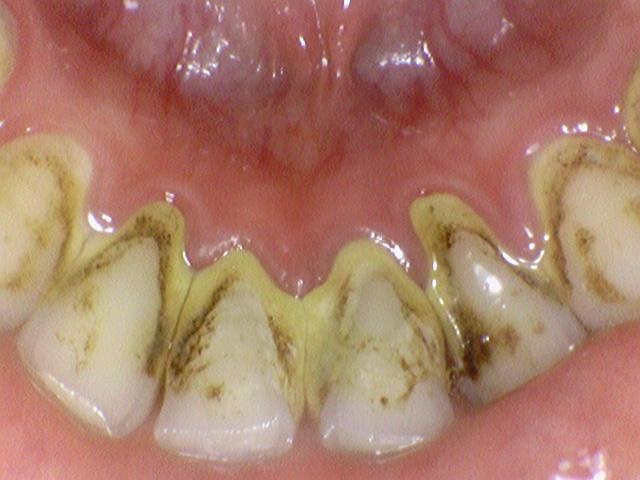

안쪽에도 치석이 많이 쌓여있습니다.

아래 두 사진은 이 환자가 저희 치과에서 스케일링을 받고 난 전 후 사진입니다.

광화문 가까운 연세예감 치과 스케일링 전후사진